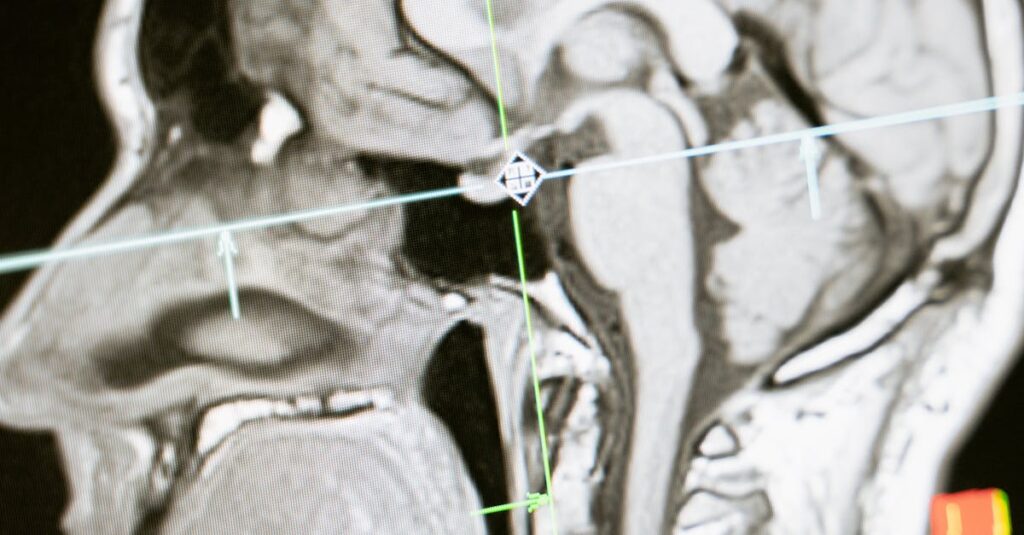

Quels examens permettent de diagnostiquer la sciatique?

Une IRM ou une radiographie est généralement nécessaire pour confirmer la cause de la sciatique.